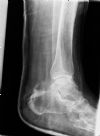

Pilon fracture. Lateral radiograph. Courtesy of Dushan Atkinson